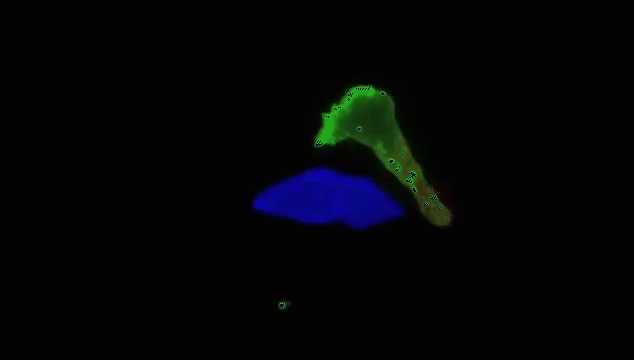

当T细胞(绿)发现癌细胞(蓝)时,通过分泌的毒素附着在癌细胞上,来检测、分辨正常细胞与癌细胞。

查明之后,T细胞(红)连接癌细胞(蓝),打破癌细胞外壁,向其表面引入毒性蛋白。